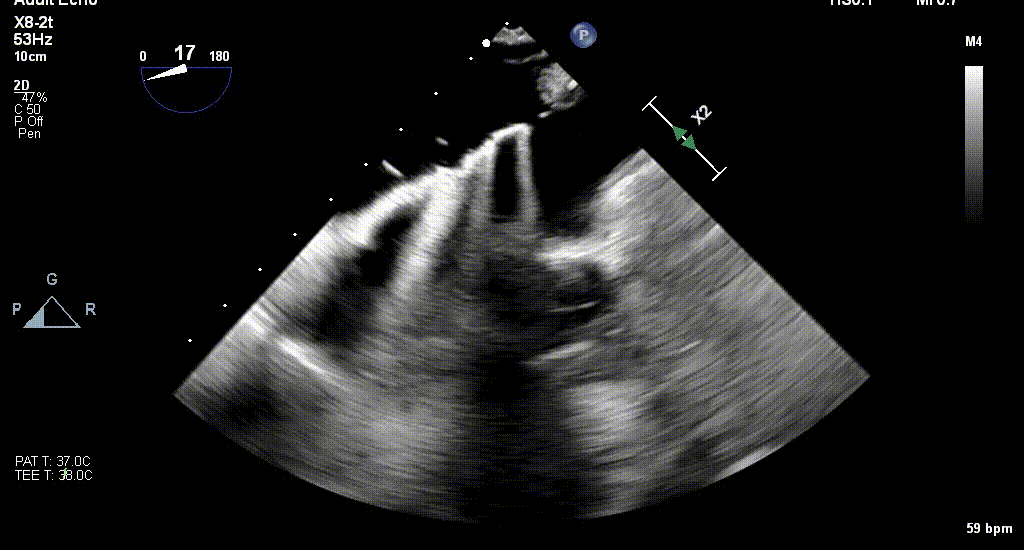

患者全身麻醉消毒铺巾后,超声引导下建立右侧股静脉入路,在经食道超声指导下精准穿刺房间隔。将可操控导引导管SGC和二尖瓣夹输送系统NTR送入左心房。

王建安教授调整二尖瓣夹轨迹和方向,使其轨迹垂直于二尖瓣环平面且指向心尖,定位于二尖瓣C1区且指向1-7点钟方位。